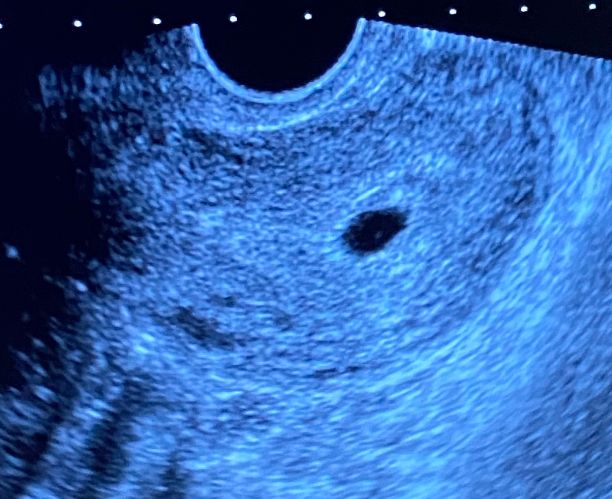

так ждала первое узи, а в итоге вообще спокойствия не добавилось! Конечно обрадовало, что беременность маточная. Но когда сказали повторно пройти узи и не визуализируется желточный мешочек и сам эмбрион-я поплыла. Знаю что нервничать нельзя, но не могу НЕдумать. Конечно начитавшись интернета были другие ожидания. Там уже и про размеры и про сердцебиение, а у меня скажем так…ничего😔еще неделю как-то нужно доходить до узи, а я переживаю так…

Жм видят примерно когда ПЯ 1-1.2 см, потом появится эмбрион, потом сб. У вас ещё рановато, через несколько дней, всё появится.

Так у вас же срок маленький,по месячным 5,3 эмбриона на таком сроке нет ещё,это рано,у меня в 5,1 пя 8 мм было,жм 1,6 был бы хуже аппарат жм могли такого размера не рассмотреть,через 9 дней в 6,3 был уже и эмбрион 5 мм и сб

Внутри ПЯ видна же какая то точечка, сходите к другому врачу, может аппарат не очень)